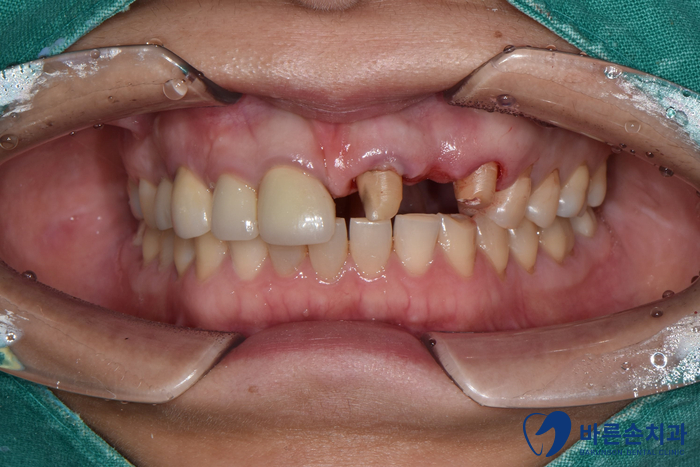

상태 체크를 위해 구내 사진과 엑스레이 촬영을 먼저 하였습니다!

치아 한 개가 상실되어 양 옆 치아를 연결해서 만든 보철물을 브릿지라고 하는데요.

브릿지가 빠져있고 남아있는 치아를 보니 연결해서 쓰던 치아 내부에 2차 충치가 생겼습니다.

사실 상태가 좋지 않아 발치 가능성이 높았지만 최대한 자연 치아를 살려보고자 치료를 들어갔어요 ‘-‘

이미 상실된 가운데 치아에는 임플란트,

양 쪽 2개 치아는 신경치료 한 후 다시 크라운 치료를 하기로 합니다.